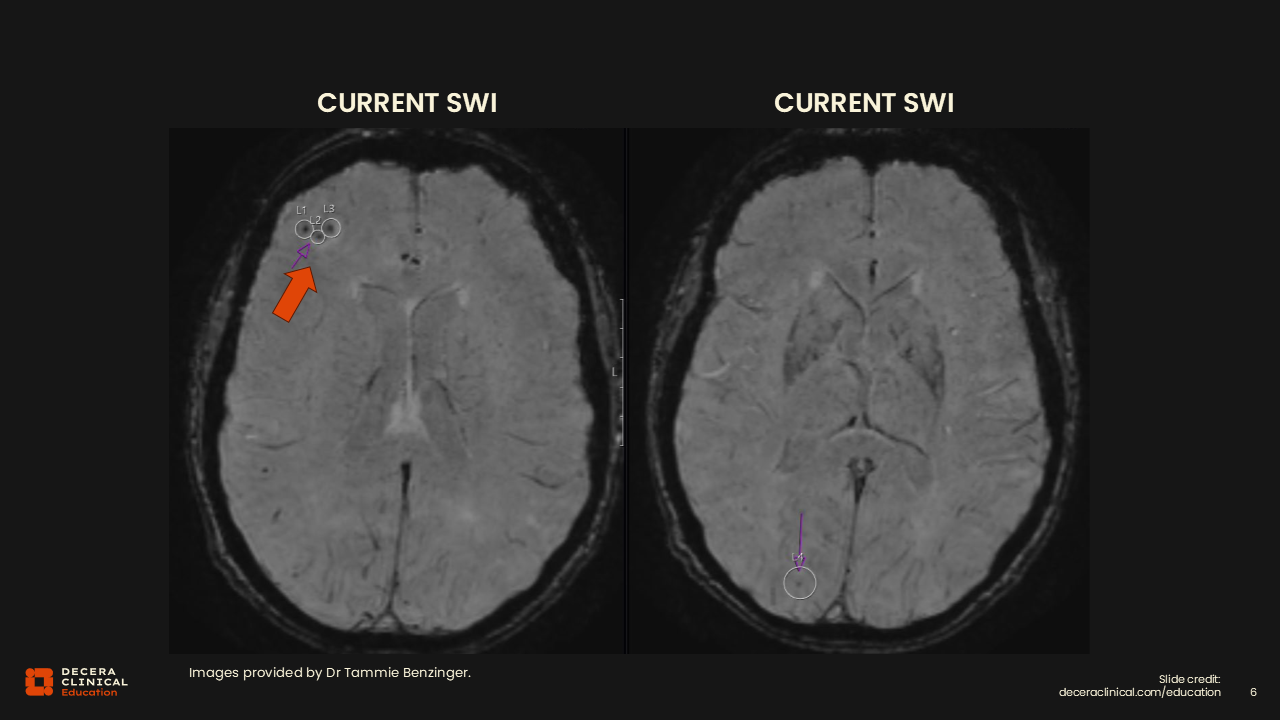

The prior MRI, which is in the lower row, is normal. With the help of the arrows, it is very clear on the follow-up scans that now there are ARIA-E both frontally and in the occipital region. The next step would then be to grade it and determine whether the patient has symptoms.

Dr Benzinger:

This is the tricky part because overall, we might think it looks mild. But in fact, if you have 2 separate regions of the brain, as in this case, frontal and occipital, automatically it becomes moderate according to the grading classification.

This example illustrates that visual impression alone may be misleading; radiologists must apply the formal grading scale rather than relying on subjective assessments of what appears “mild” or “moderate.”